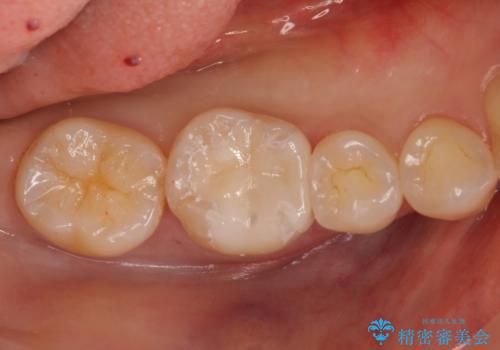

銀歯を白く セラミックインレーに

- 銀歯にしたのが20年以上前とのことで、白くやりかえたいということでした。

セラミックインレーにしています。

- 7万円(左下6 emaxプレスインレー 7万円)費用は治療当時の料金となります

銀歯を外して、下に虫歯があればしっかり取ります。しみるなどの症状が出る前がおすすめです。